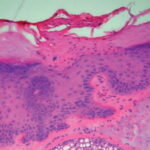

Actinic keratoses are keratinocytic dysplasias or squamous cell carcinomas in situ. This definition is preferable to their designation as precancerous because most of them never progress to cancers. Biologically, the lesions are still benign; invasion into the dermis, if present at all, is limited to the most superficial portion, the papillary dermis (see Differential Diagnosis) . |

This variety of keratosis, sometimes referred to as florid keratosis, may easily be overdiagnosed as invasive squamous cell carcinoma by the unwary. Mild or moderate papillomatosis may be present. The epidermis is thickened in most areas and shows irregular downward proliferation that is limited to the uppermost dermis and does not represent frank invasion .A varying proportion of the keratinocytes in the stratum malpighii show a loss of polarity and thus a disorderly arrangement. Some of these cells show pleomorphism and atypicality (“anaplasia”) of their nuclei, which appear large, irregular, and hyperchromatic. Often the nuclei in the basal layer are closely crowded together. Some of the cells in the midportion of the epidermis show premature keratinization, resulting in dyskeratotic cells or apoptotic bodies characterized by homogeneous, eosinophilic cytoplasm with or without a nucleus. In contrast to the epidermal keratinocytes, the cells of the hair follicles and eccrine ducts that penetrate the epidermis within actinic keratoses retain their normal appearance and keratinize normally. Occasionally, cells of the normal adnexal epithelium extend over the atypical cells of the epidermis in an umbrella-like fashion. In some cases, abnormal keratinocytes extend downward on the outside of the follicular infundibulum to the level of the sebaceous duct and, less commonly, along the eccrine duct . |

A variant of the hypertrophic type of actinic keratosis is the lichenoid actinic keratosis, which demonstrates nuclear atypia, irregular acanthosis and hyperkeratosis, the presence of basal cell liquefaction, degeneration of the basal cell layer, and a bandlike “lichenoid” infiltrate in close apposition to the epidermis . Fairly numerous eosinophilic, homogeneous apoptotic bodies are seen in the upper dermis as so-called Civatte bodies. Aside from the presence of nuclear atypicality, |

there is considerable resemblance to lichen planus and benign lichenoid keratosis. An additional distinguishing feature may be the presence of plasma cells in the lichenoid infiltrate. |